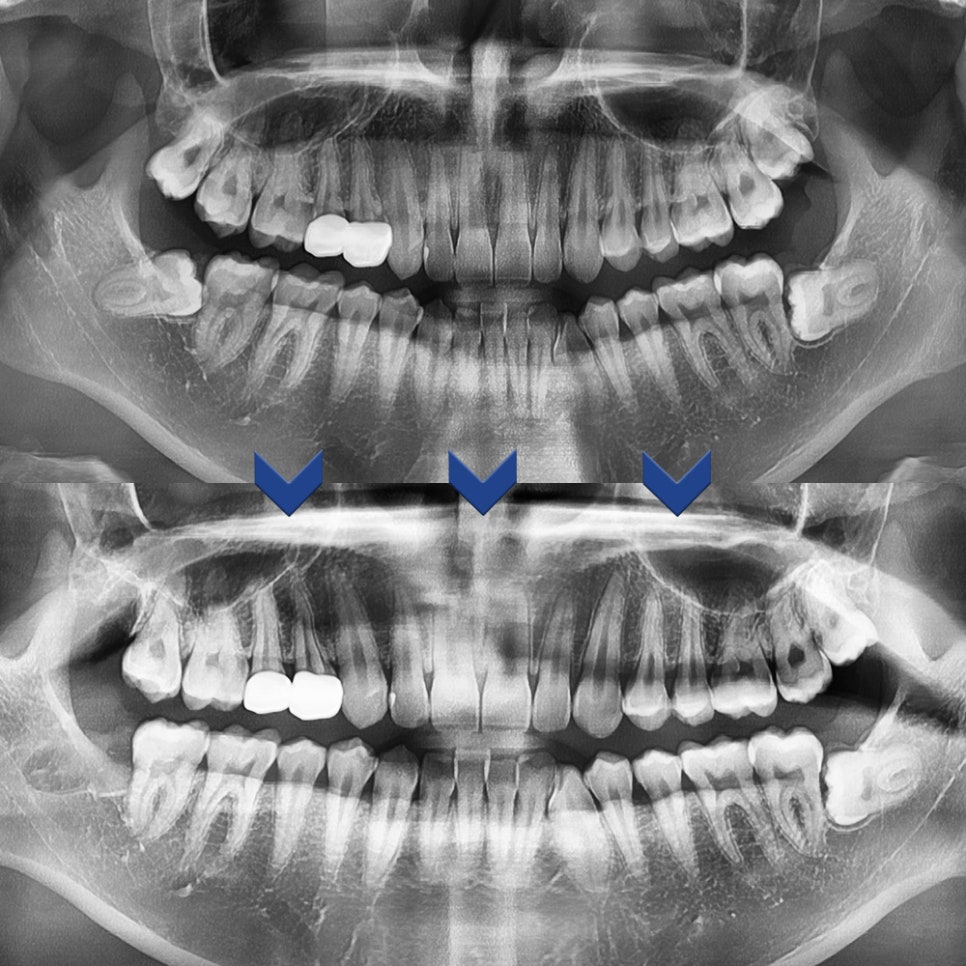

두 환자분께서 위아래 사랑니 모두 발치를 진행한 엑스레이 사진입니다

발치 후의 엑스레이 사진에서 보이시다시피

잔존 치아 없이 깨끗하게 사랑니 발치가 된 것을 확인할 수 있습니다